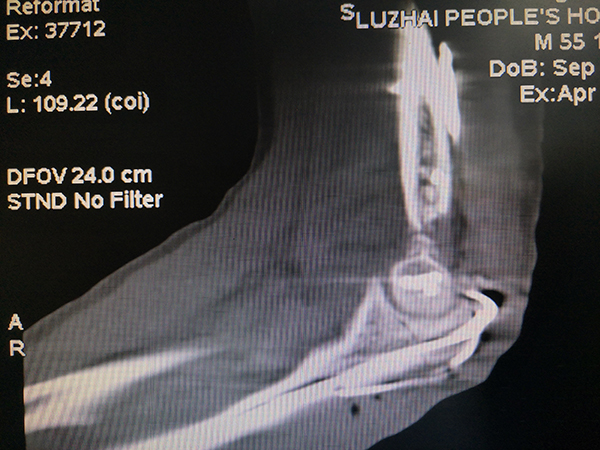

今年4月中旬,一名患者因交通意外被送入鹿寨縣人民醫(yī)院骨科,經(jīng)醫(yī)生初步診斷,該患者全身有多處骨折,其中較嚴重的是一處左肱骨遠端開放性粉碎性骨折伴骨質(zhì)缺損。

圖為 患者受傷部位圖,即左手肘部關(guān)節(jié)呈開放性、粉碎性骨折并伴有骨質(zhì)缺損